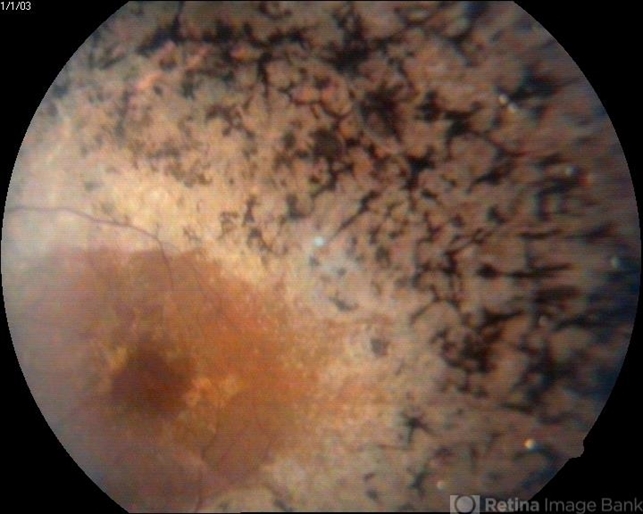

- retinitis pigmentosa (RP) dystrophy

- A 35-year-old female presented with gradual reduction in vision.